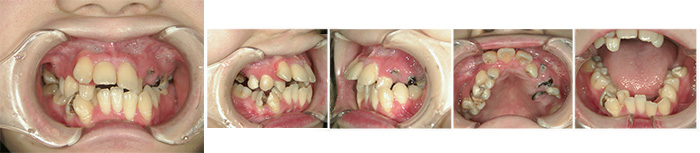

before

初診時の◯◯さんは、おそらく成長期の喘息のせいでもあろうが、歯列不正も重度であり、咬合もままならないのである。

御本人は、そもそも歯医者が大の苦手であった。それでも矯正、補綴を駆使した、長期にわたるフルバージョン歯科治療を頑張ってくれたのだ。